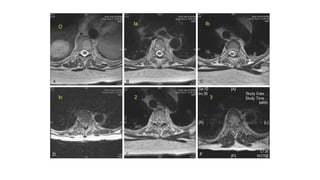

NEUROLOGIC ASSESSMENT

• six-point grading system designed and validated by the Spine Oncology Study Group

(SOSG) to describe the degree of Epidural Spinal Cord Compression (ESCC).

• This system uses axial T2-weighted images at the site of most severe compression

Epidural Spinal Cord Compression (ESCC)

grading

O

Ia

3

2

Ic

Ib

• Grades 0, 1a, and 1b - radiation as initial treatment (In the absence of

mechanical instability)

• Grades 2 and 3 (high-grade ESCC) - surgical decompression prior to

radiation therapy (unless the tumor is highly radiosensitive).

• Grade 1c - The role of surgery and radiosurgery is illdefined, but the

integration of high-dose hypofractionated radiation may allow

administration of SRS while avoiding spinal cord toxicity.